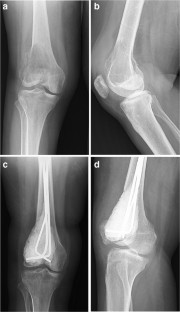

Fig. 2